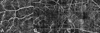

Purpose: To describe image artifacts of optical coherence tomography (OCT) angiography and their underlying causative mechanisms. To establish a common vocabulary for the artifacts observed.

Methods: The methods by which OCT angiography images are acquired, generated, and displayed are reviewed as are the mechanisms by which each or all of these methods can produce extraneous image information. A common set of terminology is proposed and used.

Results: Optical coherence tomography angiography uses motion contrast to image blood flow and thereby images the vasculature without the need for a contrast agent. Artifacts are very common and can arise from the OCT image acquisition, intrinsic characteristics of the eye, eye motion, image processing, and display strategies. Optical coherence tomography image acquisition for angiography takes more time than simple structural scans and necessitates trade-offs in flow resolution, scan quality, and speed. An important set of artifacts are projection artifacts in which images of blood vessels seem at erroneous locations. Image processing used for OCT angiography can alter vascular appearance through segmentation defects, and because of image display strategies can give false impressions of the density and location of vessels. Eye motion leads to discontinuities in displayed data. Optical coherence tomography angiography artifacts can be detected by interactive evaluation of the images.